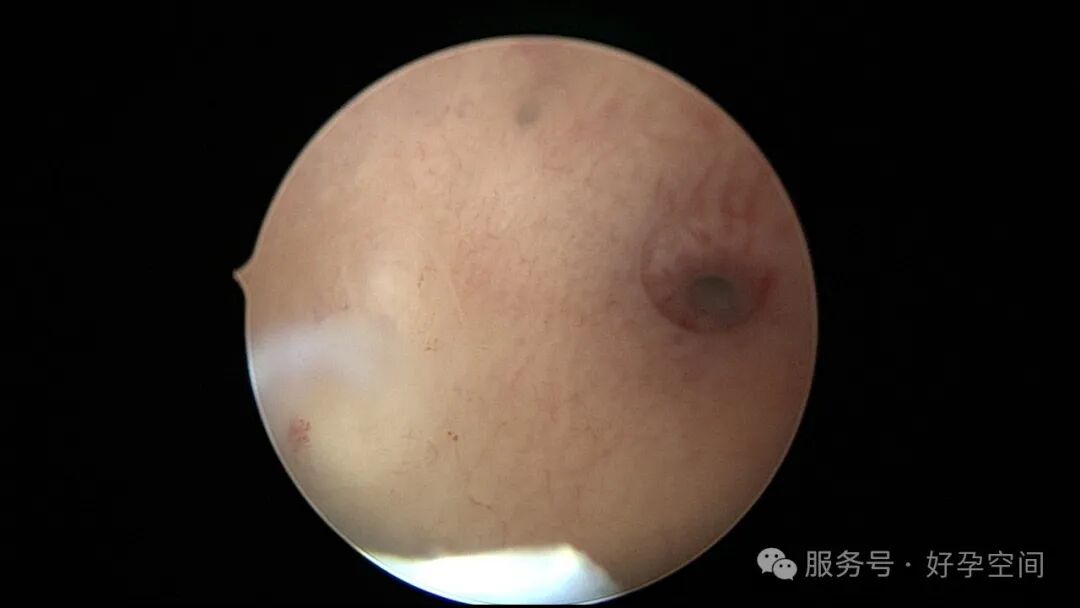

输卵管吻合术后妊娠,稽留流产,清宫术后宫腔粘连,宫腔镜单极电针分粘

分粘后宫腔镜二探,残留少许膜性粘连,镜鞘分粘

试管前宫腔镜检查